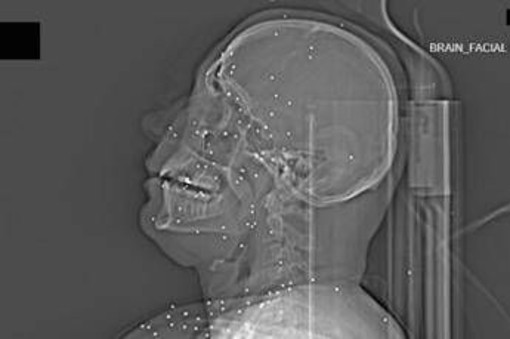

Il volto di Anahita – nome di fantasia, poco più che ventenne – appare come un cielo notturno attraversato da punti luminosi. Piccole sfere metalliche, da 2 a 5 millimetri, disseminate sul viso, nelle orbite oculari, persino nella massa scura del cervello. Sono proiettili “birdshot”, pallini da caccia sparati da un fucile a pompa. A distanza ravvicinata, spiegano gli esperti, non sono affatto “meno letali”: possono frantumare ossa, devastare tessuti molli, perforare facilmente un bulbo oculare. Anahita ha perso almeno un occhio, forse entrambi.

Quell’immagine non è un caso isolato. Fa parte di oltre 75 set di esami diagnostici provenienti da un singolo ospedale di una grande città iraniana, raccolti nel corso di una sola serata, durante la stretta repressiva di gennaio. Una concentrazione temporale che, già di per sé, racconta una dinamica da “mass casualty”, evento con numerose vittime simultanee, tipico degli scenari di guerra o dei grandi disastri.